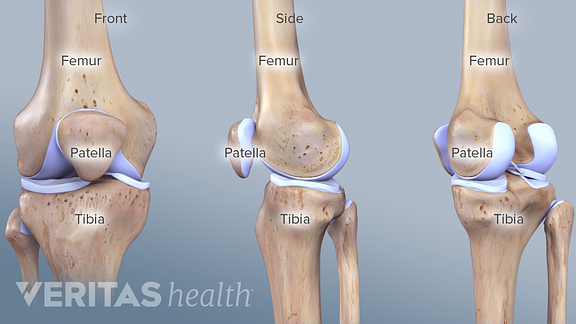

Có ba khớp ở vùng gọi là khớp gối: khớp chày đùi, khớp bánh chè đùi, và khớp chày mác trên.

Khớp chày đùi

Khớp chày đùi là khớp giữa hai xương dài nhất cơ thể, xương đùi và xương chày. Nó được xem là một khớp lồi cầu đôi hoặc khớp bản lề thay đổi kết hợp một bản lề và một khớp xoay. Ở khớp gối, gấp và duỗi xảy ra tương tự như khớp khuỷu, nhưng gấp kèm theo một mức độ xoay nhỏ nhưng đáng kể.

Diện khớp:

Lồi cầu trong và lồi cầu ngoài xương đùi. Lồi cầu ngoài dẹt hơn, diện khớp lớn hơn, hướng ra sau hơn, canh thẳng với xương đùi. Lồi cầu trong dài và hướng vào trong hơn, canh thẳng với xương chày.